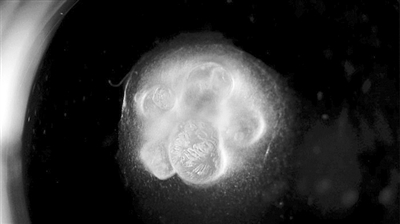

10???????????3D????????????3??????

?????2D??3D????????????????????

?????????????????????3?????????????????????